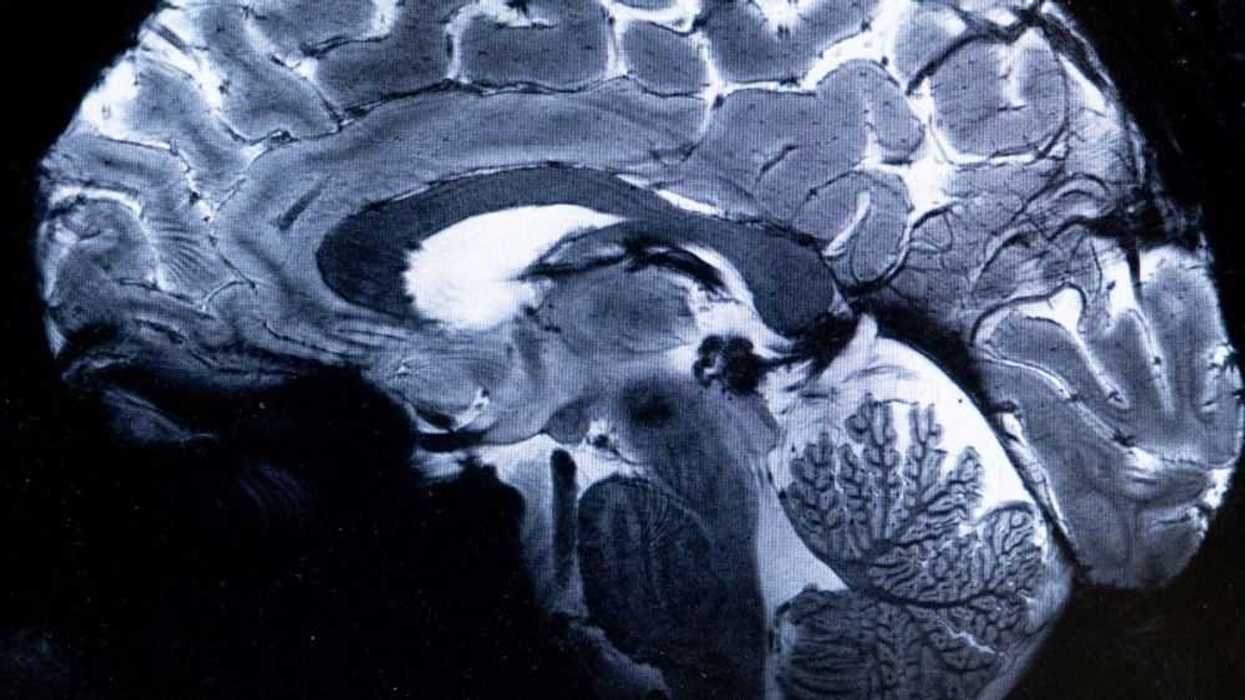

Saclay, Francia, 4 Abril 2024.- El escáner de resonancia magnética (IRM) más potente del mundo ha logrado escanear con un nivel de precisión desconocido el cerebro humano, anunciaron sus responsables en Francia, una tarea que podría ser decisiva para detectar enfermedades.

Esta potencia permite que la máquina escanee imágenes 10 veces más precisas que los IRM utilizados en hospitales, cuya potencia normalmente no supera los tres teslas.

En una pantalla de computadora, Vignaud comparó imágenes tomadas por este poderoso escáner, apodado Iseult, con las de un IRM normal.

"Con esta máquina podemos ver los pequeños vasos que alimentan la corteza cerebral, o detalles del cerebelo que eran casi invisibles hasta ahora", dijo.